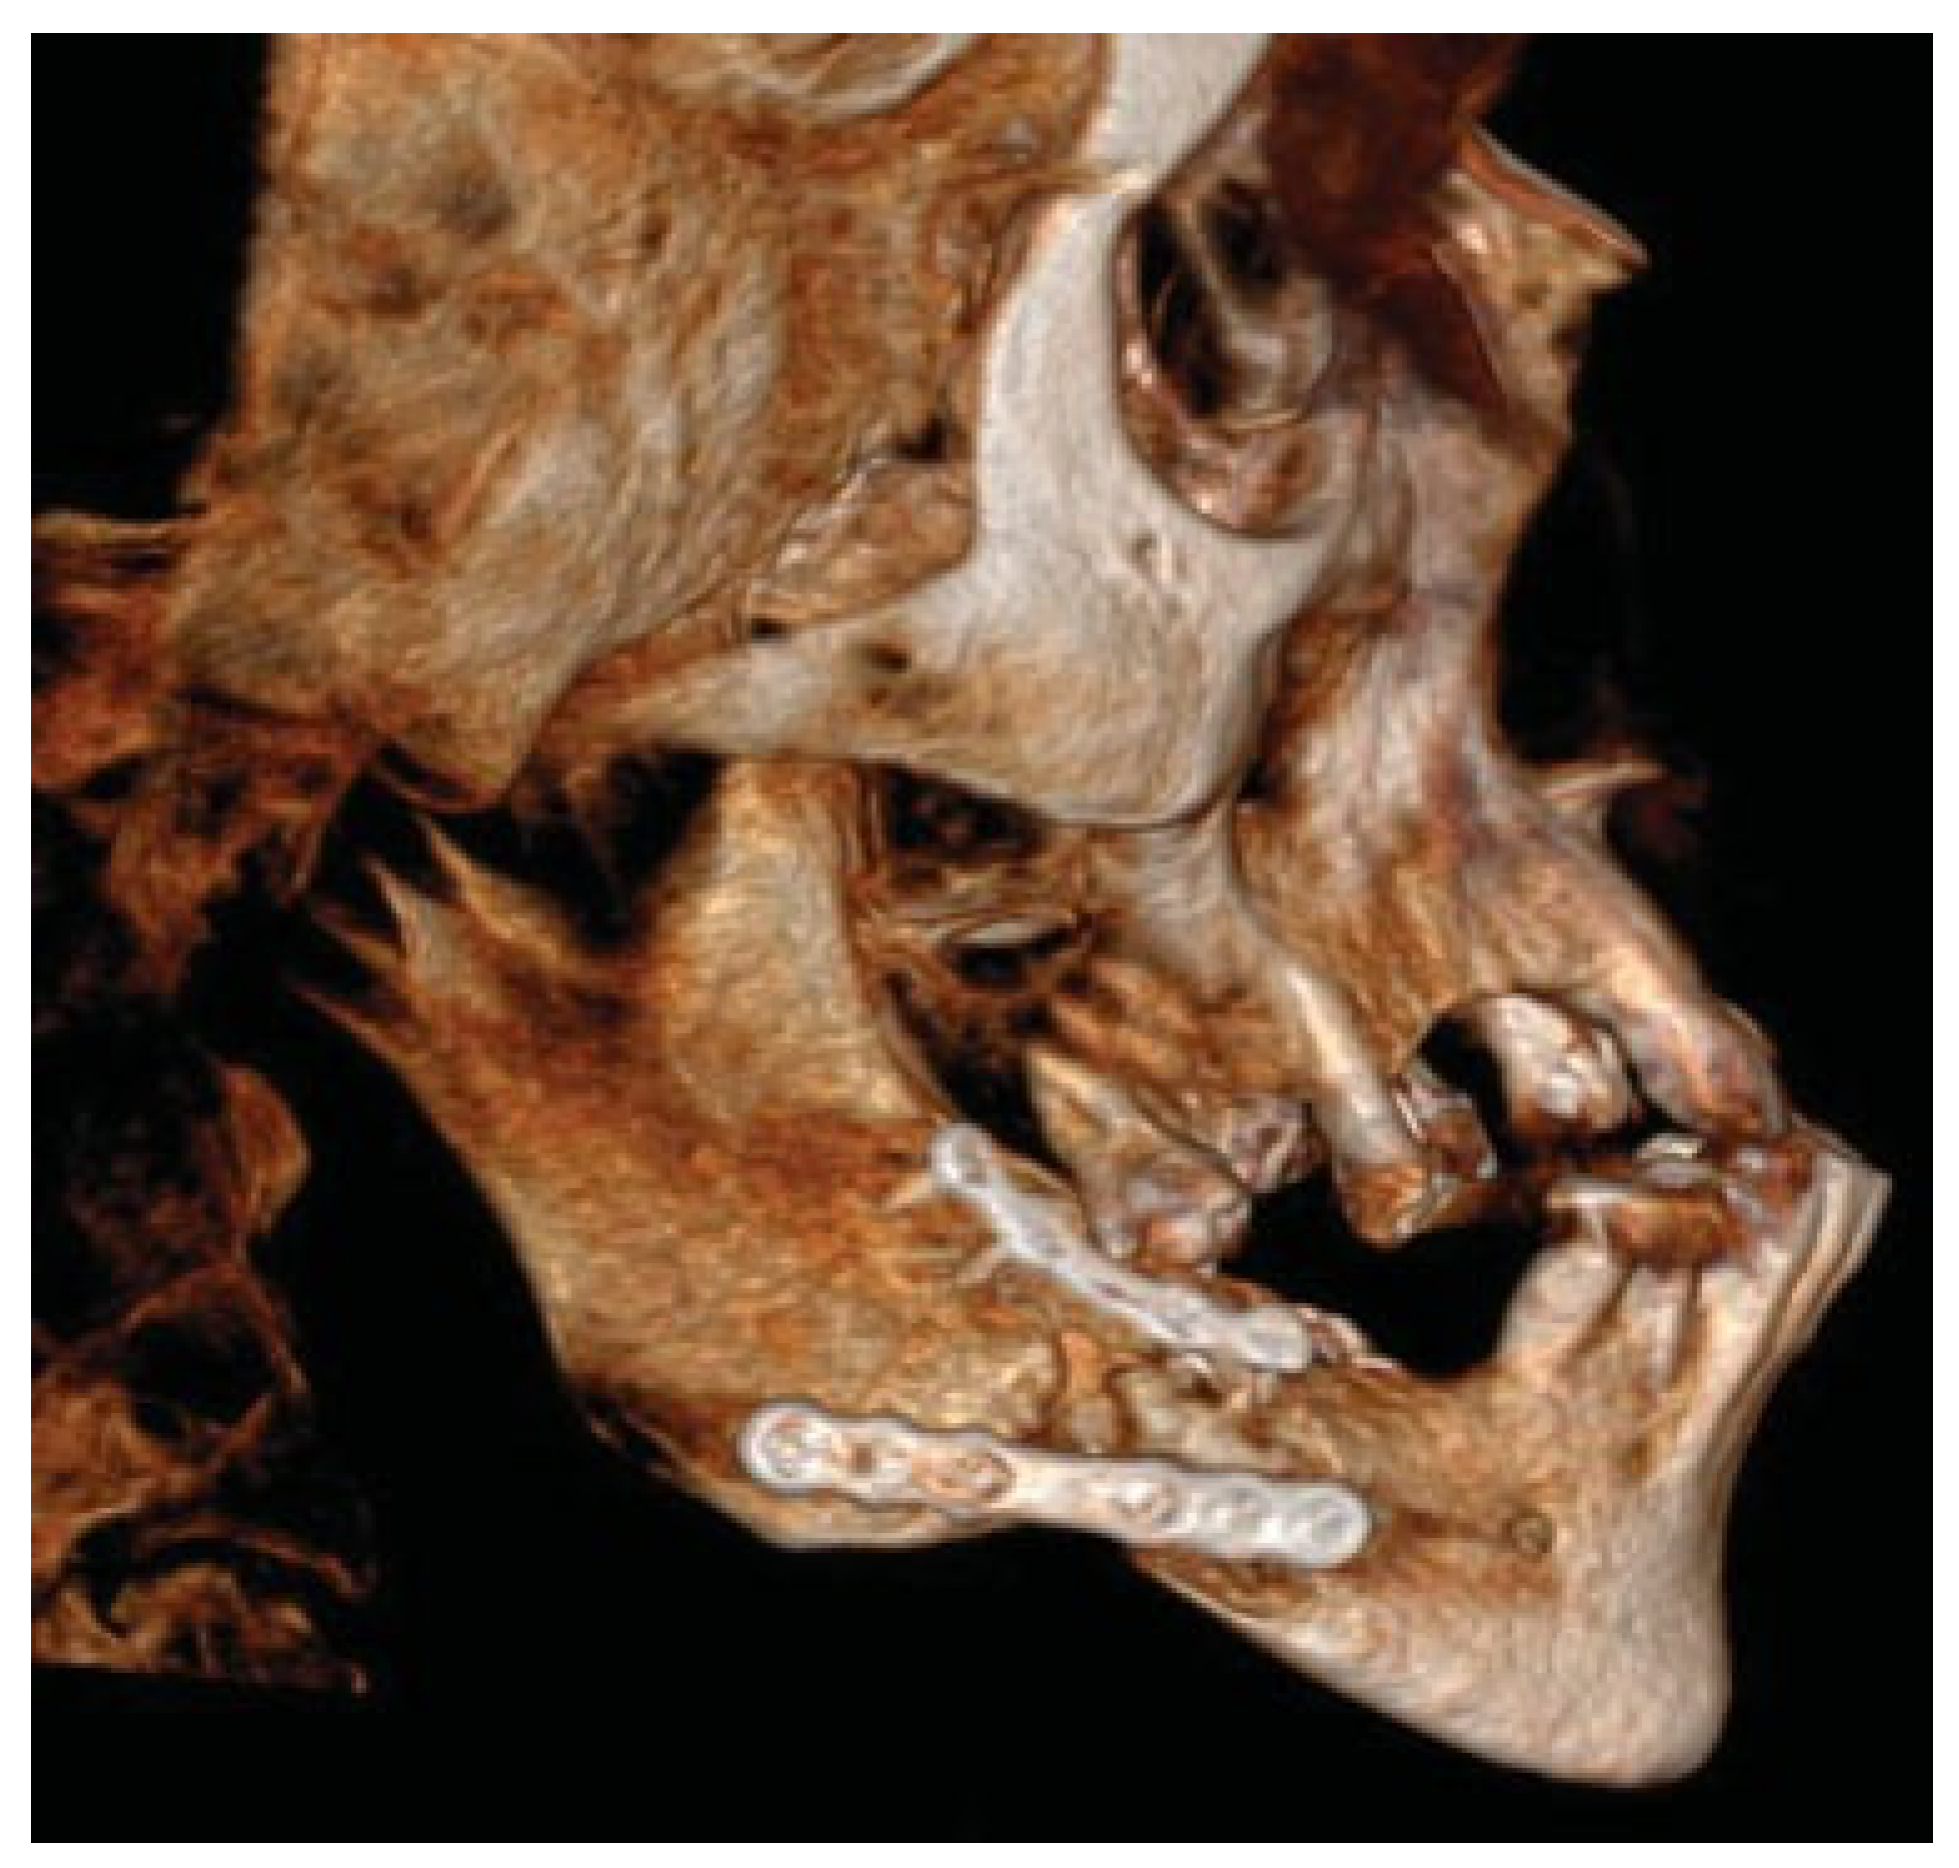

Figure 2.

Post-operative situation after bilateral intraoral plate fixation and placements of basal screws via trocar.

Figure 3.

Patient developed infections with oral mucosal fistulas in the fracture areas and an open bite. CBCT displays obvious anterior rotation of proximal segments and posterior rotation of the dentate part of mandible. Considerable muscle action creates new dislocation and is not counteracted by the inadequate osteosynthesis of the fractures.